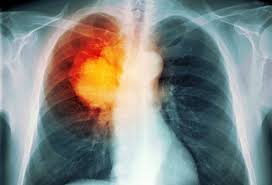

شيوه جديد براي تشخيص زودهنگام سرطان ريه

قرار است اين روش در ايندهيي نزديك جايگزين شيوههاي كنوني تشخيص سرطان نظير پرتونگاري بشود ».